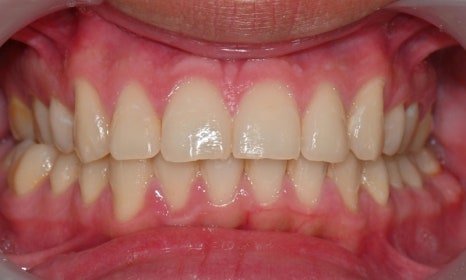

아래 앞니에 남아있는 레진 제거 후 미백 치료 결과

예전에 교정 치료를 마치고 미백을 하러 오시는 환자들을 보면, 가끔 브라켓을 뗀 이후 레진 접착제가 치아 표면에 일부 남아 있어서 그 부분이 노랗게 변색된 경우를 발견할 수 있습니다. 교정을 끝내고 브라켓을 제거한 이후에 레진 접착제를 깨끗하게 제거한 후 폴리싱을 해서 매끈하게 해주어야 하는데, 그렇지 못할 경우 남아있는 접착제에 의해 주변에 치태가 침착되거나 착색이 증가할 수 있고, 남아있는 레진이 변색될 수 있습니다. 이 경우 남아있는 레진을 제거한 후 미백을 해주게 되면 깨끗한 치아를 얻을 수 있습니다.